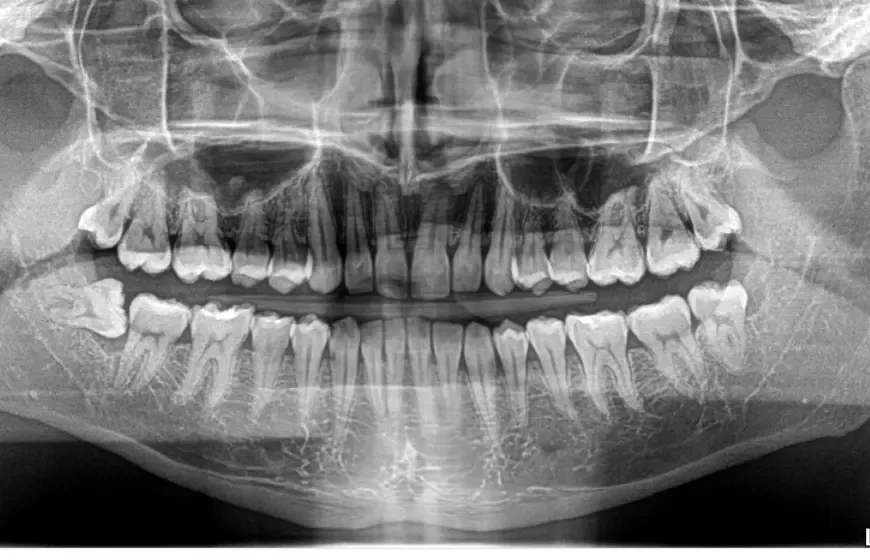

Pantomogram (panorama): Ogólny przegląd stanu uzębienia

Pantomogram, potocznie nazywany "panoramą", to zdjęcie, które daje ogólny obraz całego uzębienia, obu szczęk, zatok przynosowych, a nawet stawów skroniowo-żuchwowych. Choć nie jest tak szczegółowe jak zdjęcie punktowe, jest niezastąpione do wstępnej diagnostyki, planowania leczenia ortodontycznego, protetycznego czy implantologicznego. Pozwala mi szybko ocenić obecność wszystkich zębów (w tym zatrzymanych ósemek), ogólny stan kości, a także wykryć większe zmiany patologiczne, takie jak torbiele czy nowotwory. To takie "zdjęcie lotnicze" całej jamy ustnej.